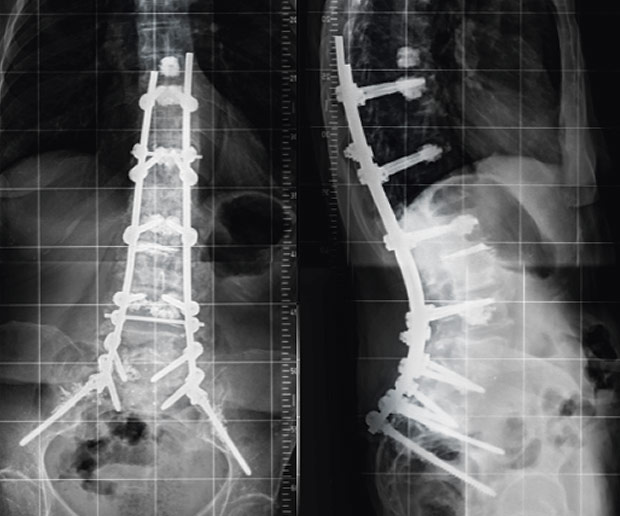

Diese Wirbelbrüche sind zwar nicht instabil und die Gefahr von Schäden am Rückenmark ist sehr gering dennoch können sie starke Schmerzen und eine Fehlstellung der Wirbelsäule verursachen. Er kann an einem der sieben Halswirbel entstehen. Bei jüngeren Betroffenen sind in der Regel Verkehrs- und Sportunfälle die Ursachen für einen Wirbelbruch bei älteren Menschen geht ein Wirbelbruch vor allem auf eine schwache Knochenstruktur durch Osteoporose zurück.

Diese Wirbelbrüche sind zwar nicht instabil und die Gefahr von Schäden am Rückenmark ist sehr gering dennoch können sie starke Schmerzen und eine Fehlstellung der Wirbelsäule verursachen.

Er kann an einem der sieben Halswirbel entstehen. Der erste Halswirbel wird als Atlas bezeichnet der zweite als Axis. Dieser Bereich stellt den oberen Teil der Wirbelsäule dar der aus den Wirbelkörpern Bandscheiben Muskeln Bändern und den Nervenbahnen besteht. Denn der Eingriff birgt Risiken gerade für ältere Betroffene die Operationen nicht mehr so gut verkraften. Er kann an einem der sieben Halswirbel entstehen. Die Schmerzen können einen älteren Menschen ans Bett fesseln und seiner Mobilität berauben und hier lauert die eigentliche Gefahr. Nur 15 bis 20 Prozent aller Wirbelsäulenverletzungen betreffen die Halswirbelsäule. Unter einem Genickbruch versteht man allgemein einen Bruch der Halswirbelsäule. Diese Wirbelbrüche sind zwar nicht instabil und die Gefahr von Schäden am Rückenmark ist sehr gering dennoch können sie starke Schmerzen und eine Fehlstellung der Wirbelsäule verursachen.